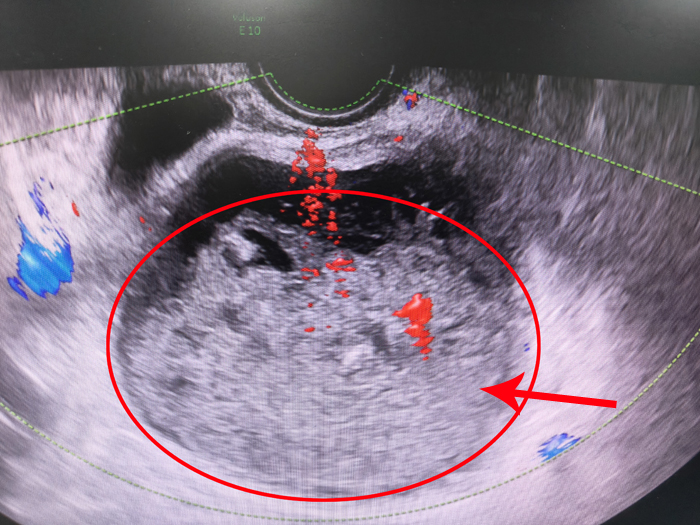

年近70岁的肖女士近两个月阴道间断性有脓性液体流出,因伴随腹痛难忍且有发热症状,便在当地医院进行口服抗生素等治疗十多天,但症状却愈加严重。肖女士的女儿带着她辗转来到潞河医院急诊就诊。经入院检查,肖女士合并有高血压、冠心病(冠脉支架置入术后)、慢性肾功能不全多种合并症,B超提示宫腔液性暗区7.2*8.3*7.9cm,透声差,血白细胞计数20.13*109/L。妇产科主任高洁认真查看患者情况后,考虑宫腔大量积脓,且已经出现了脓毒血症,同时伴有肾功能衰竭、心绞痛症状,病情十分危重,即刻上报医疗部。医疗部主任刘淼高度重视,立即组织肾内科、心内科、重症监护室、感染性疾病科等多学科会诊,经多学科讨论后一致认为当务之急是加强抗感染力度,控制合并症,积极宫腔引流放脓。与此同时,高洁紧急联系超声科为肖女士进行超声引导下宫腔置管引流术。但由于患者绝经多年导致阴道狭窄宫颈萎缩,大量积脓导致宫体过度膨胀,肌层糟脆如豆渣,手术操作难度和风险极大。妇科治疗组凭借着精准技术,伴随着超声科医生的一声赞叹:“太棒了,置管已顺利进入宫腔!”大量恶臭的黄绿色脓液随之顺管缓缓流出,肖女士的腹痛感瞬时好转。随后在重症监护室治疗期间,肖女士在医护人员的精心治疗和护理下顺利闯过了脓毒性休克、心绞痛、心功能不全、呼吸衰竭、下肢深静脉血栓形成等多重难关,病情稳定后顺利出院。

一个月后,肖女士来到高洁主任门诊复查,超声及核磁检查再次提示宫腔积脓,虽然无腹痛及发热不适,但宫腔积脓极易复发的特点展现无疑,将来极有可能再次发展成脓毒血症,甚至危及生命。接下来该怎么办?做手术切除子宫可以切除感染灶,“一劳永逸”,但是由于患者合并症多,围手术期出现心血管事件甚至猝死风险极大,且患者已是慢性肾病5期(尿毒症),手术麻醉难度及风险极大;宫腔引流+静脉抗炎保守治疗?治疗风险低,但效果不佳,病情容易反复加重。高洁反复细致多次与患者及家属沟通医疗风险利弊及其他替代治疗方案的风险,患者家属非常理解病情的危重并坚定地对高洁说:“第一次来住院,就感受到潞河医院的专业性和责任心,我们相信你们,选择手术!”。